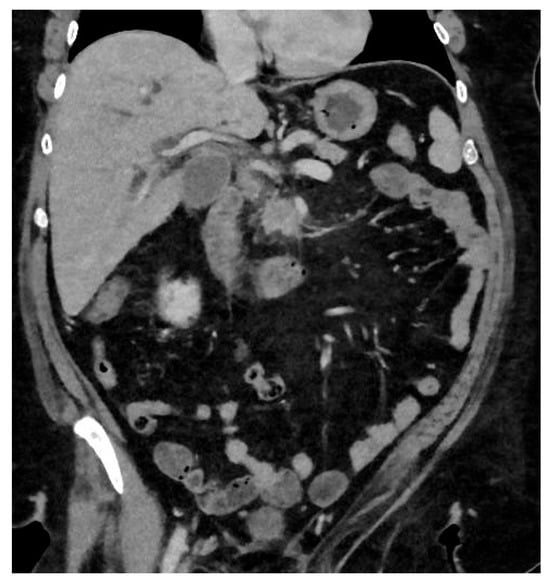

The characteristic features of IPMN are papillary proliferation of mucin-producing epithelial cells which result in cysts arising from the pancreatic ducts. The cysts can block pancreatic ducts and cause pancreatitis, which is a painful condition that is associated with both IPMN and pancreatic cancer. IPMNs are divided morphologically into 2 groups, depending on whether it is located on the main pancreatic duct or on a branch duct. IPMNs can also be mixed type and show features of both main duct and branch type architecturally. See Figure 4.

Total pancreatectomy is increasingly being offered for IPMN when it is located in the main pancreatic duct. IPMN occurring in this area anatomically, are at risk of transforming to PDAC. The practice has evolved over time, and started to be reported approximately 10 years ago [9,10]. More detailed indications were outlined in 2018 [11].

Figure 4. Total pancreatectomy for main duct IPMN.